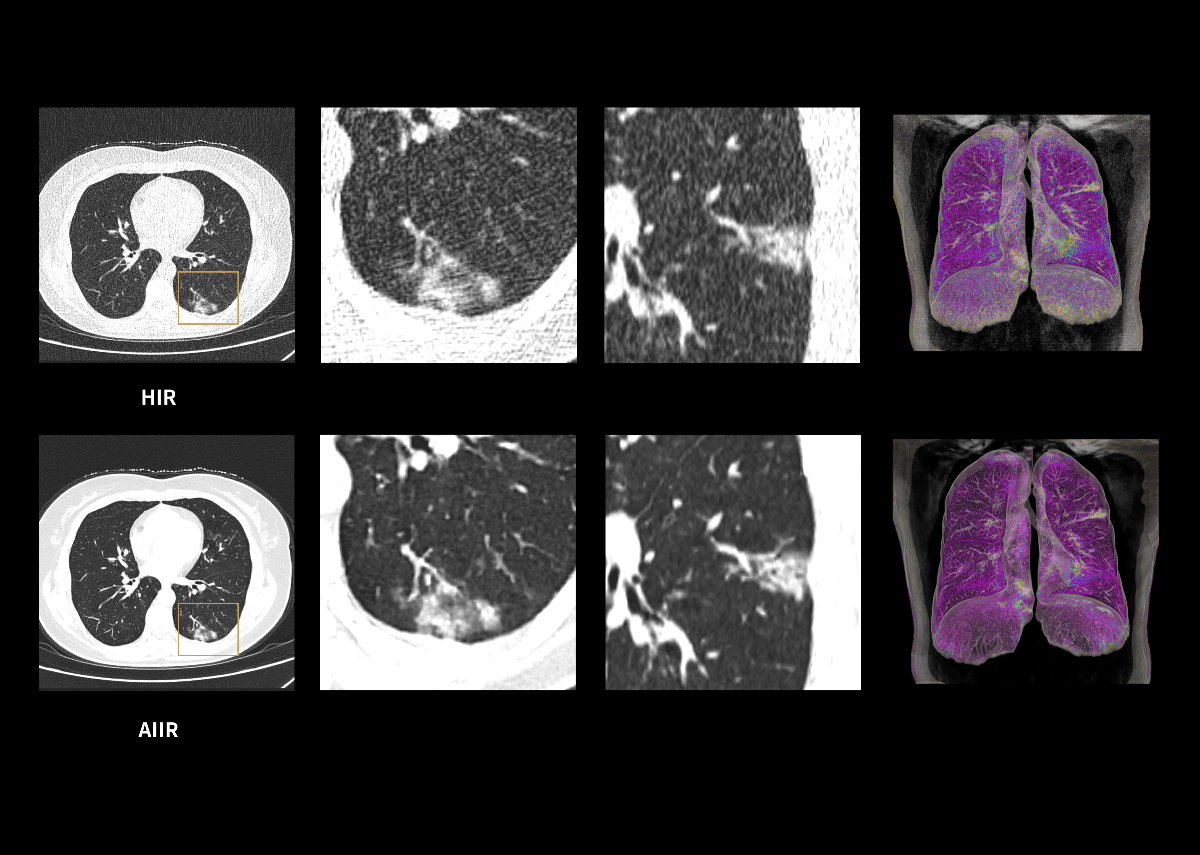

AIIR* – AI Iterative Reconstruction

Throughout the iterative loop of forward and backward projection between the raw data domain and the image domain, AIIR consistently takes into account the accurate modeling of optics, noise, anatomy, and physics statistics. Additionally, AIIR integrates deep learning-based de-noising technology, supplanting the conventional regularization role of MBIR in the optimization reconstruction process.

In brief, AIIR utilizes deep learning-based AI technology to attain robust noise reduction and natural image texture, while incorporating MBIR technology to achieve precise anatomical structure representation and artifact suppression. This technique surpasses the limitations of using either MBIR or deep learning reconstruction (DLR) independently.